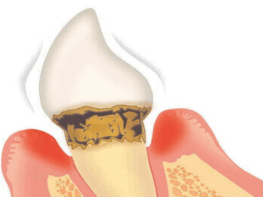

【重度歯周炎】

歯槽骨で歯を支えられなくなる

重度になると更に症状が進行し、顎の骨が半分以上溶けています。歯周ポケットが更に深くなり歯ぐきが退縮して歯のグラつきが悪化します。歯肉からは膿が出るので口臭がきつくなり、治療せずに放置していると最終的には歯が抜け落ちる事もあります。